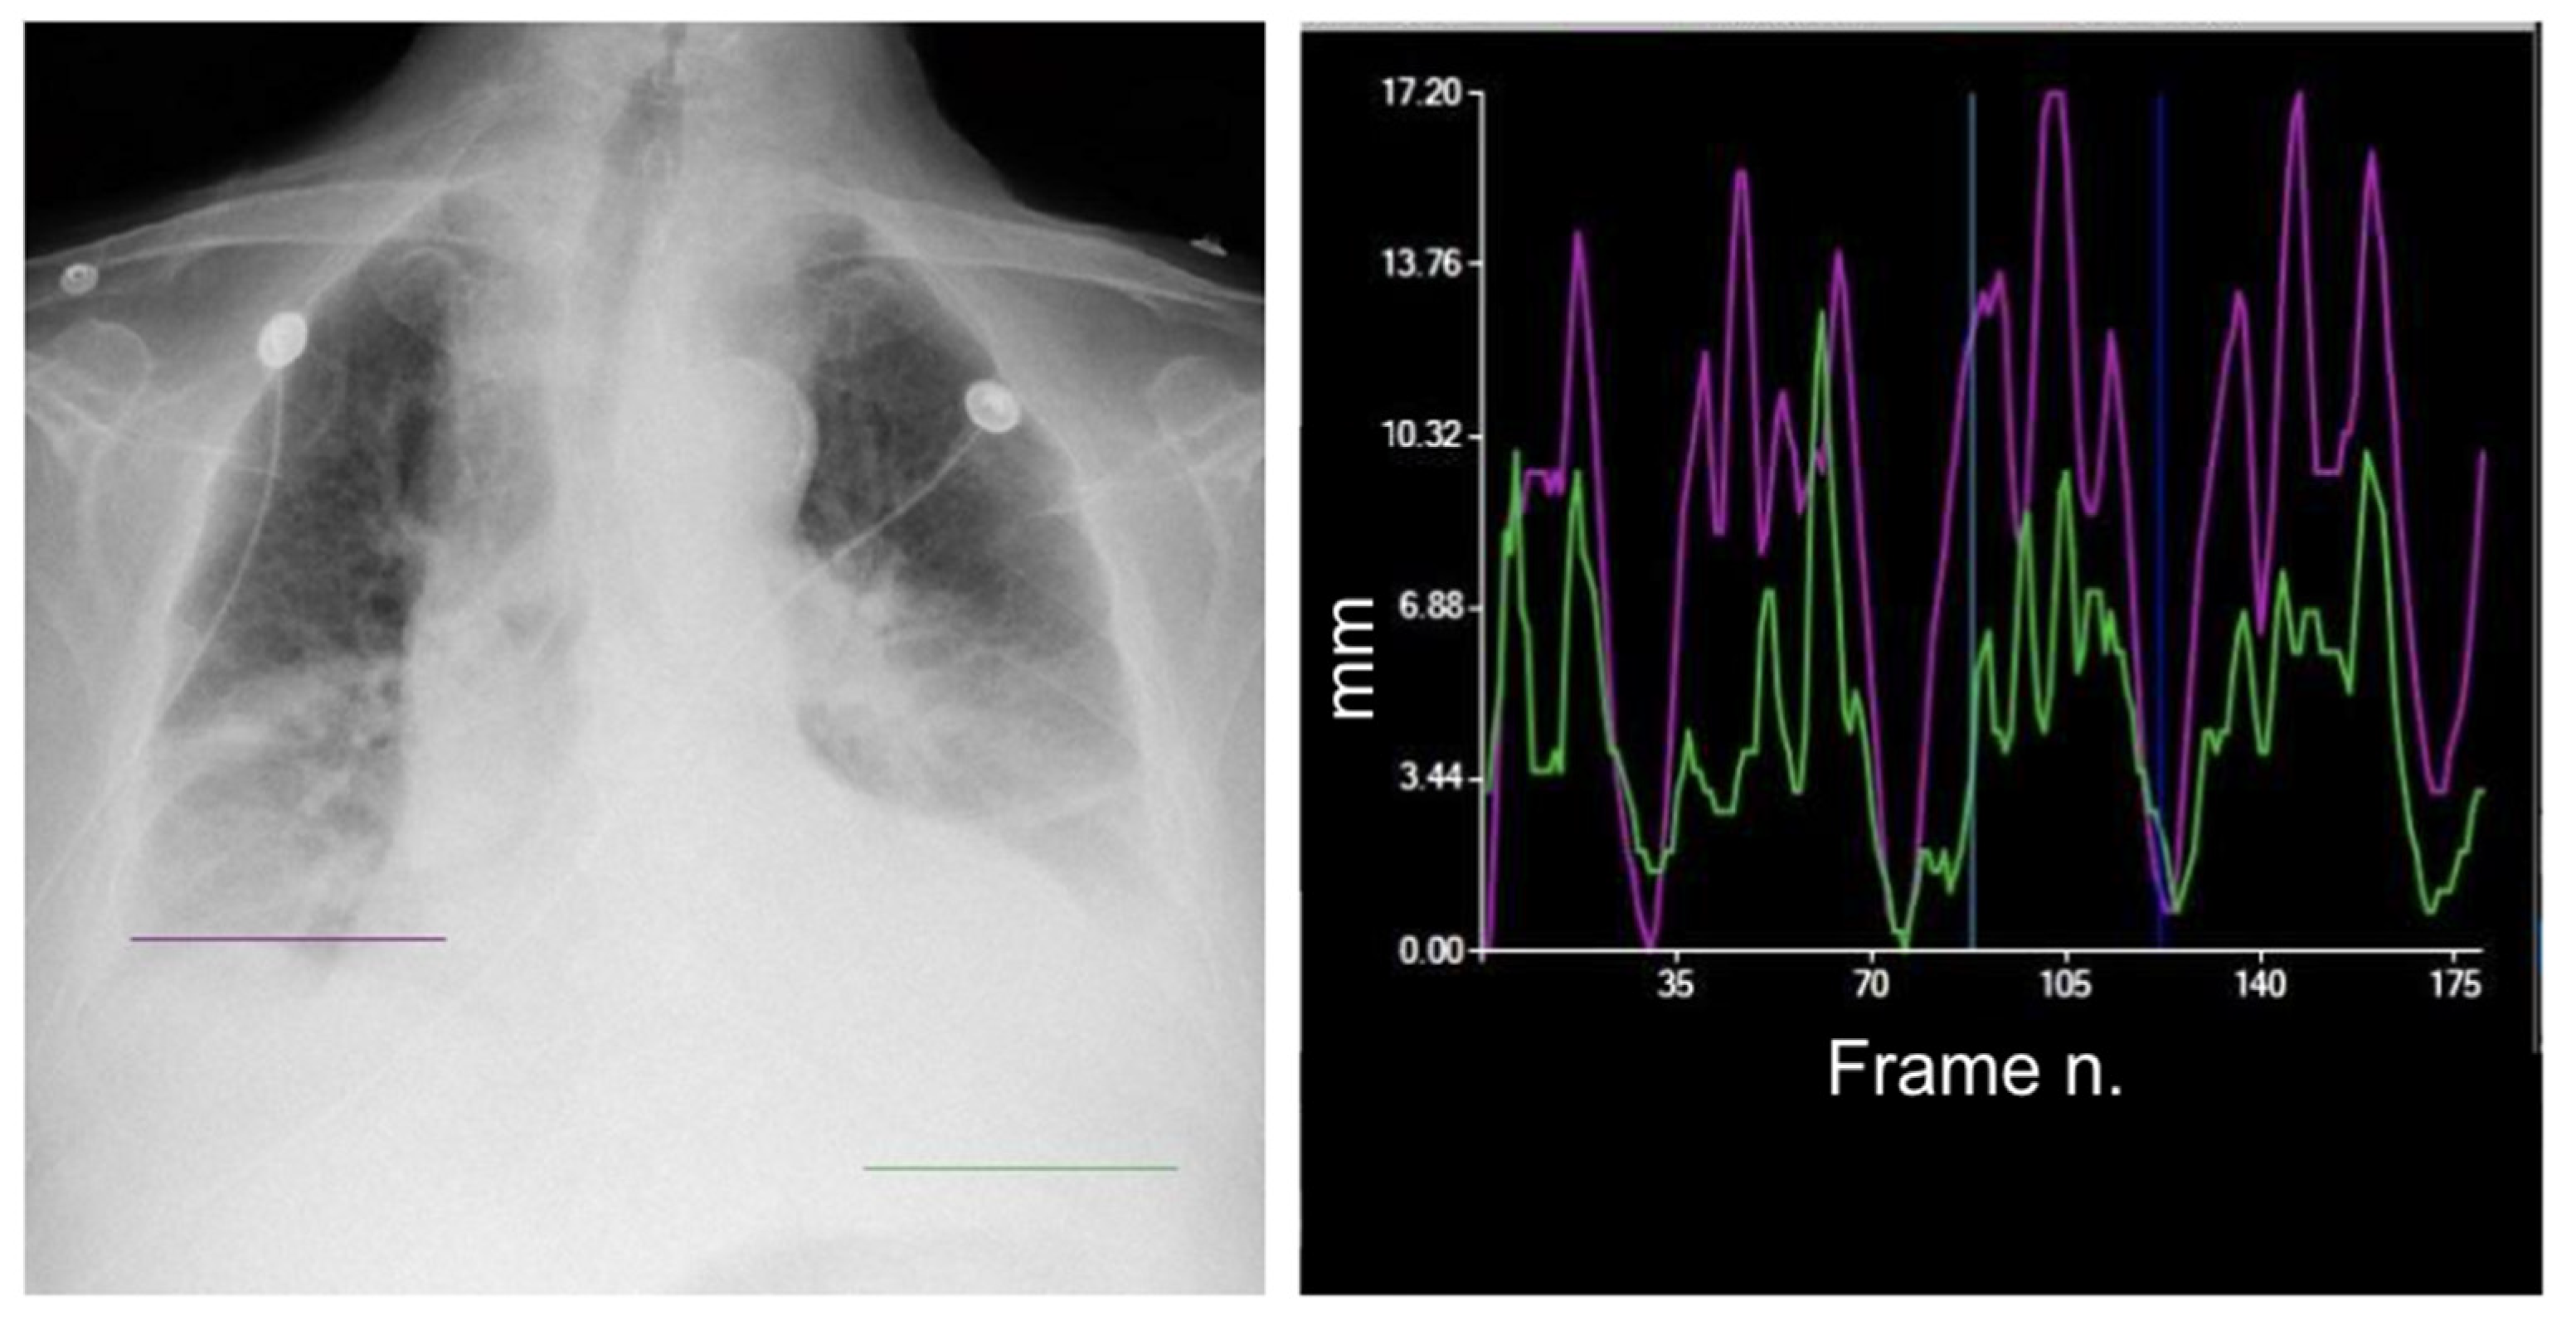

2. The Equipment

| DM-mode | Tracking diaphragm motion. Automatic calculation of the lung area and the relative changing rate (%). | Tracking of diaphragmatic domes represented in a motion–time graph. Area detection through an edge detection method in the post processing phase. | Diagnosis of diaphragm motion impairment and palsy. Automatic calculation of the respiratory rate. Analysis of lung dynamics in patients with restrictive/obstructive diseases. Follow-up of patients in pulmonary rehabilitation. |